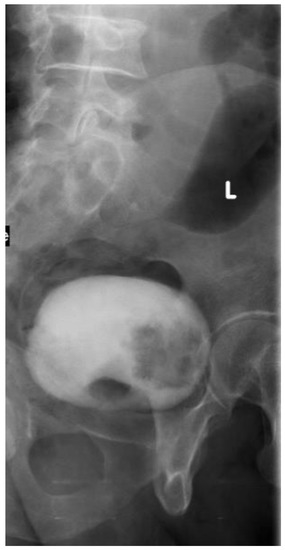

2.1. Plain X-ray

2.2. Intravenous Urography “IVU”